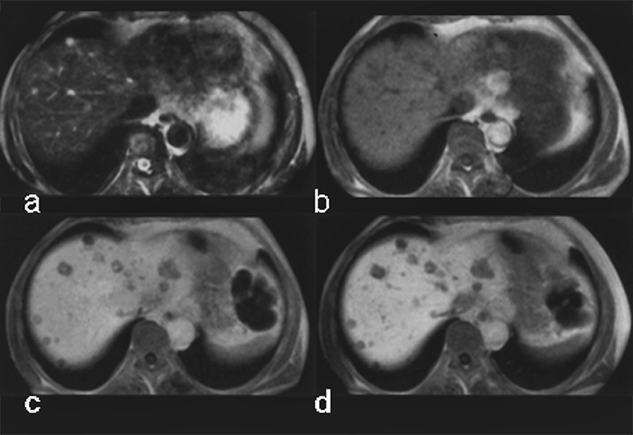

Although the chemical composition of Gd-BOPTA appears similar to that of the extracellular gadolinium agents, it combines both extracellular and liver-targeted properties, because some 5% of it is excreted through the liver, as is shown in this case of multiple metastases (Figure 13-14).

Figure 13-14:

Gadolinium-BOPTA in liver metastases of a pancreatic tumor.

(a) plain T1-weighted GRE sequence; (b) plain T2-weighted GRE sequence; (c) enhanced T1-weighted GRE sequence 40 minutes after injection; (d) T1-weighted GRE sequence 90 minutes after injection.